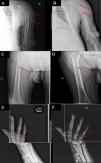

Describimos el caso de un varón de 52 años con dolor osteomuscular de predominio en cintura escapular y en ambas manos que se exacerbaba durante las sesiones de hemodiálisis. El paciente tenía múltiples factores de riesgo cardiovascular y enfermedad renal crónica secundaria a reflujo vesicoureteral. Trasplantado renal en dos ocasiones, con disfunción crónica de ambos injertos. Adicionalmente, presentaba hiperparatiroidismo terciario, persistente. Se realizó paratiroidectomía subtotal, con exeresis de 4 glándulas paratiroides en 2012, nueva resección de glándula hiperplásica en 2021 y termoablación de hiperplasia paratiroidea superior izquierda en 2022. Tras 5 meses con etelcalcetide la PTH se redujo desde 831pg/ml hasta 286pg/ml. Fue diagnosticado de síndrome de túnel del carpo, que requirió exoneurólisis. Dadas las características del dolor, el tiempo acumulado en hemodiálisis de 22años y la presencia de síndrome de túnel carpiano, se realizó control radiológico, observándose lesiones radiolúcidas en diáfisis de huesos largos, junto con datos de resorción subperióstica (fig. 1). Con estos hallazgos se sospechó amiloidosis β2m concomitante con enfermedad ósea metabólica de alto remodelado. No fue posible la obtención de muestras para diagnóstico histológico. Se inició tratamiento con doxiciclina a dosis bajas y se aumentó el número de sesiones de hemodiafiltración on-line a cuatro sesiones semanales por negativa del paciente a realizarse mayor número. El paciente presentó un curso clínico favorable, con reducción en el dolor reportado mediante escala visual analógica del dolor, pasando de 9 a 6 puntos. Transcurrido un mes del incremento de las sesiones de hemodiálisis on-line, la concentración sérica prediálisis de β2m se redujo de 41,7mg/l a 32,2mg/l, un descenso del 22%. Tras un año de intensificación del tratamiento y 13 meses de doxiciclina, se observó una mejoría e incluso la desaparición de las lesiones óseas en la radiografía de húmero izquierdo (fig. 1A-B), del fémur derecho (fig. 1C-D) y de la falange media del quinto dedo de la mano derecha (fig. 1E-F).